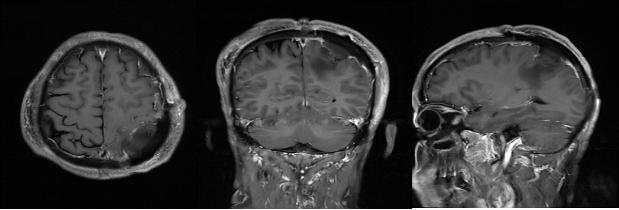

术后复查,肿瘤一级切除